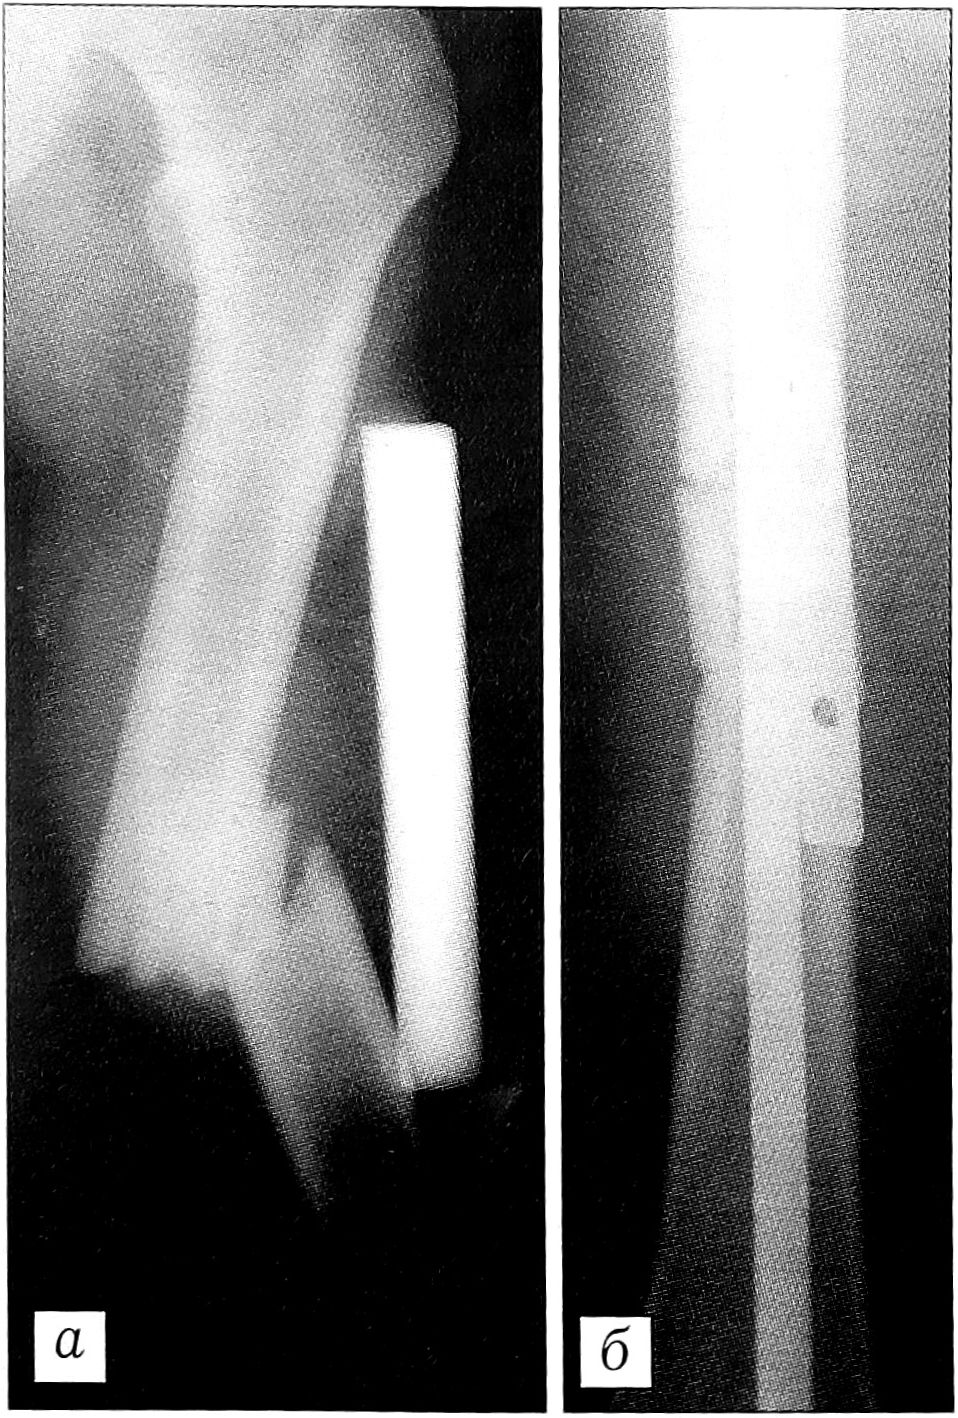

Возможности оперативного лечения переломов значительно расширялись при использовании закрытого остеосинтеза с блокированием (42 операции), который можно считать методом выбора у пострадавших с политравмой, поскольку он не сопровождается кровопотерей, обеспечивает прочную фиксацию отломков и позволяет в максимально ранние сроки после операции активизировать больного. При выполнении закрытого остеосинтеза с блокированием мы допускали наличие в зоне перелома кровоподтеков, ссадин, фликтен.

Клинический пример. Больной Л.,23 лет, поступил в реанимационное отделение НИИ СП им. Н.В. Склифосовского через 1,5 ч с момента получения травмы (попал в автоаварию, находясь за рулем мотоцикла). В результате обследования поставлен диагноз: сочетанная травма, сотрясение головного мозга, перелом VI—VII ребер справа с повреждением ткани легкого, правосторонний пневмоторакс, закрытый оскольчатый перелом правого бедра (тип В по классификации АО), закрытый перелом левого бедра (тип А), закрытый оскольчатый перелом левой голени (тип В) (рис. 2, а, в, д). При поступлении больному проводились противошоковые мероприятия, в том числе анестезия мест переломов, дренирование правой плевральной полости; для иммобилизации переломов бедер и голени было наложено скелетное вытяжение. На 5-е сутки дренаж из плевральной полости удален. На 10-е сутки под спинномозговой анестезией произведен одномоментно закрытый блокирующий остеосинтез обоих бедер и левой большеберцовой кости гвоздями без рассверливания костномозгового канала (рис. 2, б, г, е). Перед операцией НЬ 87 г/л, Нt 29%. Во время операции переливались свежезамороженная плазма (725 мл) и эритроцитная масса (200 мл). После операции НЬ 92 г/л, Ht 30%. Ранний послеоперационный период протекал без осложнений. Движения в смежных суставах начаты на 3-й день после операции. Швы сняты на 12-е сутки. Заживление послеоперационных ран первичным натяжением. Через 13 дней после операции у больного выявлен окклюзионный тромбоз общей бедренной вены слева. Проводилась консервативная терапия. Через 48 дней после операции больной активизирован — начал вставать и учиться ходить с дополнительной опорой на костыли. На 63-й день после получения травмы пациент выписан на амбулаторное лечение в удовлетворительном состоянии, с полным восстановлением движений в суставах конечностей.

Рис. 2. Рентгенограммы больного Л. Оскольчатый перелом правого бедра (а — при поступлении, б— после закрытого остеосинтеза с блокированием); перелом левого бедра (в — при поступлении, г — после закрытого остеосинтеза с блокированием); оскольчатый перелом костей левой голени (д — при поступлении, е — после закрытого остеосинтеза с блокированием).

У 8 больных наложенные на реанимационном этапе АНФ служили средством хирургической иммобилизации переломов и требовали замены на блокируемый гвоздь или пластину. Замена аппарата блокируемым гвоздем производилась на 5_ 10-е сутки, пластиной — на 3-4-й неделе после травмы.